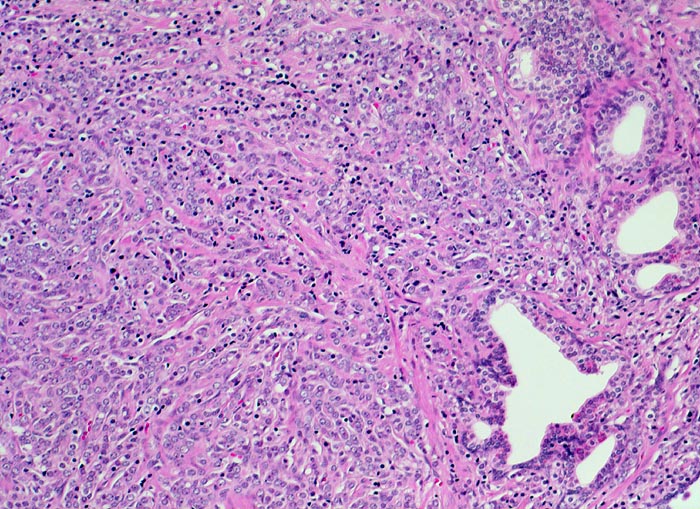

• Herde kleiner Karzinomdrüsen ohne Basalzellschicht.

• Fehlende lobuläre Anordnung der Karzinomdrüsen.

• Karzinomzellen mit stark erhöhter Kern-Zytoplasmarelation und hyperchromatischen Zellkernen mit grossen eosinophilen Nukleolen.

• Wenig differenzierte Karzinomanteile ohne erkennbare Drüsenbildung.

• Perineuralscheideninvasion.